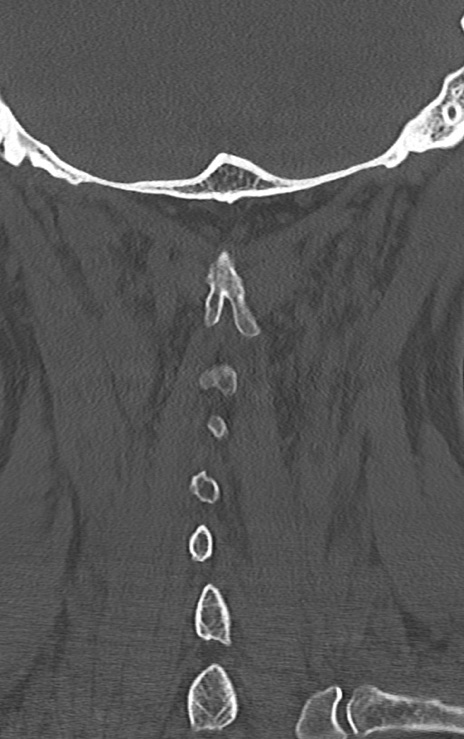

頚椎CT

矢状断像